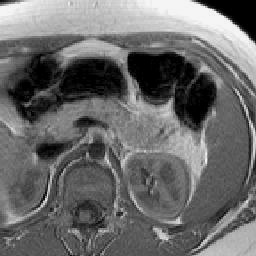

Finally, Fig. 9 displays examples of output probability maps from all of the comparative methods, i.e., HNN [12], UNet [16], PNet-MSA and “PNet-MSA+BiRNN”, where the latter one delivers the sharpest and clearest output on both CT and MRI datasets. More specifically, PNet-MSA presents results that are detailed and recover the major part of the pancreas, where both HNN and UNet suffer from significant low segmentation recall. When observing the BiRNN outputs for CT and MRI, we find detailed pancreas parts in CT have been recovered via shape continuity learning and regularization, while in MRI, the BiRNN only outputs probability map with the same shape in PNet-MSA’s output, which is optimal when the inter-slice shape changes drastically in the MRI dataset. Thus, BiRNN would help to refine pancreas segmentation with a smoothed surface in the situation that slice thickness of the 3D scans is reasonably small, e.g., <2absent2<2mm.

Figure 9: Examples of output probability map: columns from left to right are the input CT/MRI image, results from HNN [12], UNET [16], the proposed PNet-MSA sub-network, and the full CNN-RNN (“PNet-MSA+BiRNN”), and the ground truth. Our model delivers the most clear probability maps which preserve detailed pancreatic boundaries.